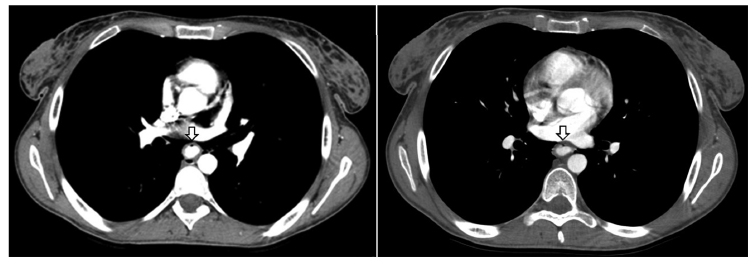

El esófago se encuentra dilatado en toda su extensión con el contenido de contraste hasta su tercio superior. Se observa una laceración esofágica en la cara anterior, en su tercio inferior, a 65 mm de la unión gastroesofágica (Figura 2). Se identifica abundante contenido de material de contraste en la cámara gástrica, asociado a las suturas mecánicas a su alrededor y una distensión del asa anastomosada, observando una oclusión intestinal del asa aferente (Figura 3).